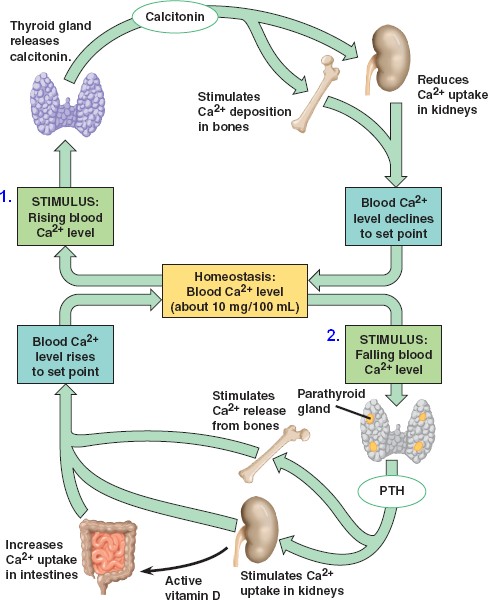

45_11CalciumHomeostasis_L

homeostasis-calcium.html